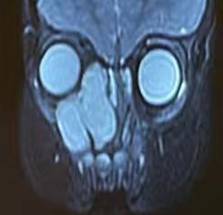

此例患者年龄为1岁3个月,右侧面部隆起,眼球突出,1个月内进展迅速,为婴儿罕见病例。患儿及家属辗转于省内多家医院,最终入住西安交通大学第一附属医院耳鼻咽喉头颈外科,权芳主任医师带领的团队在经全科讨论后,最终制定了以手术为主的治疗方案。由于患儿年龄小,且肿瘤范围大,血供丰富,有效循环血量仅800ml,术中出血成为最为关注的问题,且止血难度极大,术后感染不易控制,患儿配合差。术前在权芳主任医师的组织下进行了多学科(影像科、眼科、血管外科、麻醉科、中心ICU、新生儿科等)会诊讨论,对患者的术前评估、手术方式、手术可能出现的并发症、术后处理措施及围手术期患者的全身管理及护理等方面做了充分的准备,并制定了多种意外情况下的备用方案。

术后病理报告为富含粘液及血管的间叶源性肿瘤,经免疫组化和二代全基因测序,诊断为世界罕见的婴儿原始黏液样间叶性肿瘤,目前世界范围内共计报道30余例,多数患儿预后差,完整切除为首选治疗方案,化疗效果不确定,尚无统一指南建议。因此准确及时的诊断及手术至关重要,对该肿瘤的生物学行为和预后的明确认识还有赖于长期随访和更多病例的积累。